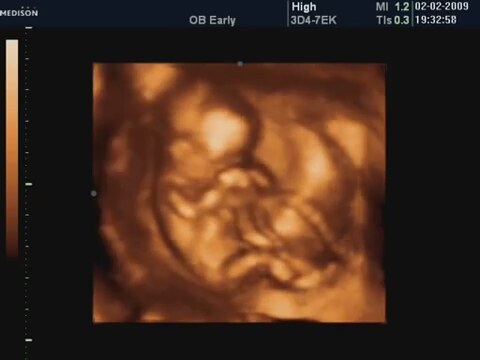

19 Haftalik Bebeğin 4 Boyutlu Ultrason Görüntüsü